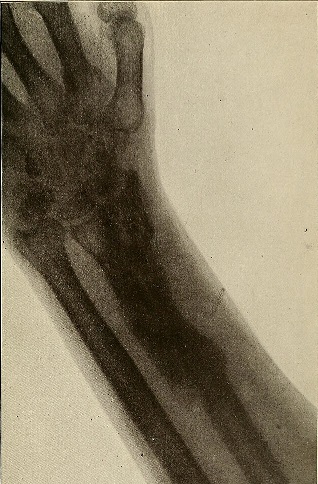

겨울엔 몸이 굳어있고 미끄러운 곳이 많아 넘어지기 쉬운 계절로 생각지도 않게 골절을 당하기 쉽습니다. 특히 폐경 이후에 골밀도가 떨어진 여성의 경우 더 쉽게 골절에 노출되며, 골프, 스키, 축구 등 많은 스포츠에서도 뼈에 금이 가는 상황이 생깁니다. 골절의 치료에 대해 적어보겠습니다.

골절에 한의학적 치료의 효과

33편의 논문에서 침치료가 통증과 일상수행능력, 삶의 질의 개선을 보였다고 합니다.